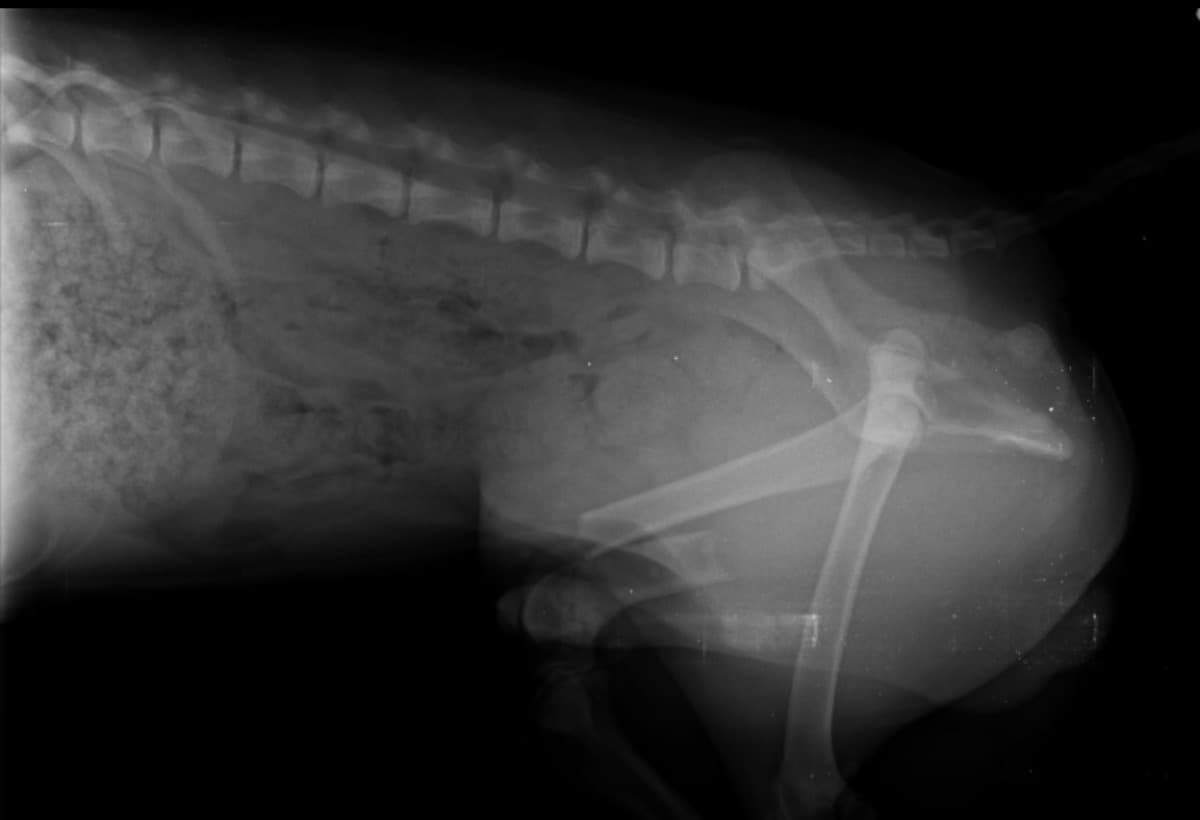

I noticed scout limping after bringing him home from playing with his friends not sure of what happened exactly but the vet estimated the cost of surgery to be around 2400-2800 with a 75% down payment needed please help before it heals the wrong way THANK YOU